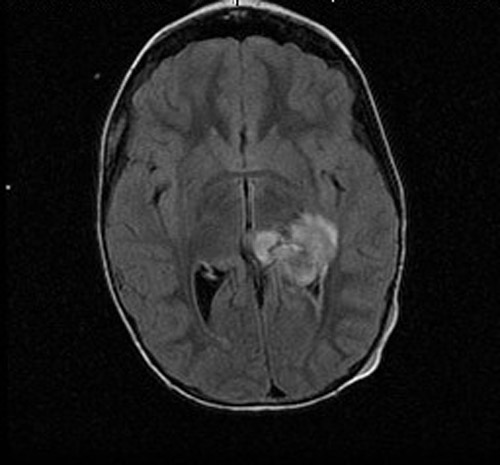

The patient was a 6 year-old girl who presented with a history of Streptococcal infection about 3 weeks ago and was treated with Amoxicillin. She improved briefly but started vomiting, hip pain, neck pain, and severe headache. She was treated with antibiotics under the impression of meningitis and she improved again. However, she started vomiting for several times again and was admitted to the emergency. An MRI scan demonstrated a brain mass as illustrated here. The lesion was excised and yielded this specimen.

• MRI studies demonstrate a 3.3 x 3.2 x 2.7 cm well-circumscribed mass in the left lateral ventricle. The tumor has both an exophytic part and parenchymal involvement of the underlying brain. This mass has heterogenous signal intensity on T1-weighed images and heterogeneous enhancement. On FLAIR images,  It causes a 0.5 cm midline shift to the right and mild dilatation of the right lateral ventricles. FLAIR images do not demonstrate excessive edema.

MRI FLAIR